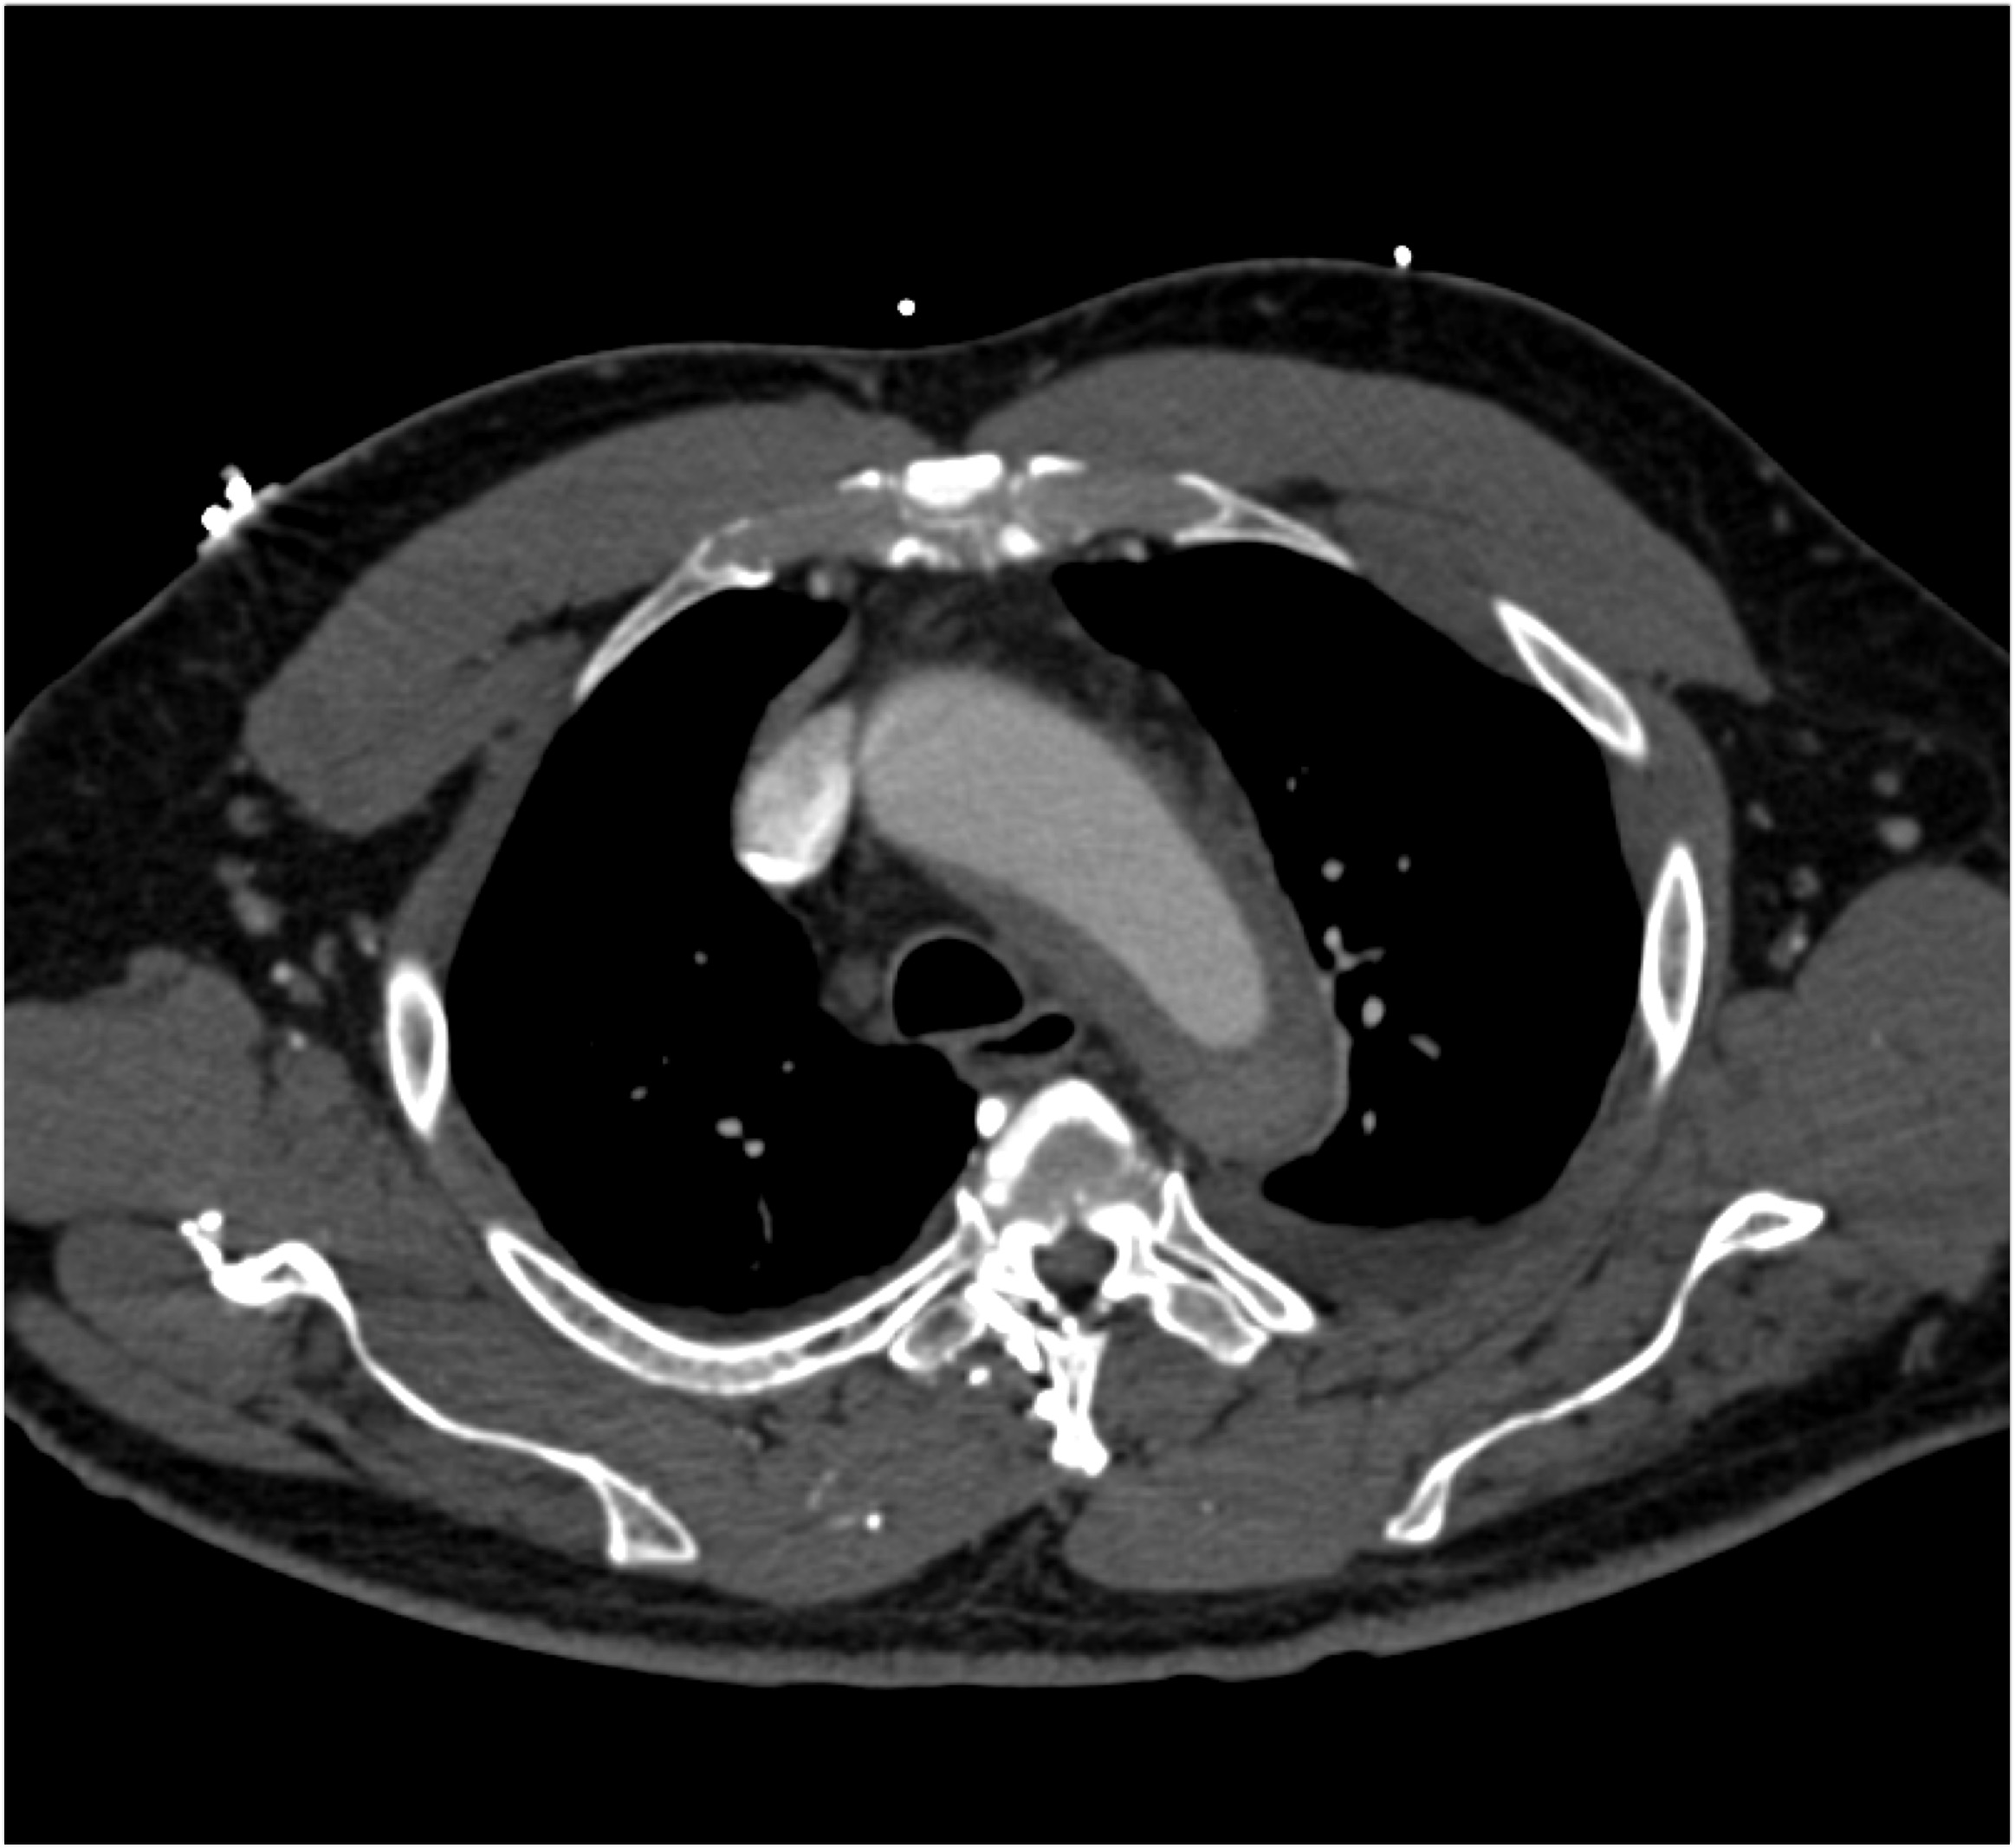

4) The most likely diagnosis in this patient with acute chest pain is?

type A dissection

intramural hematoma

type B dissection

Takayasu’s aortitis